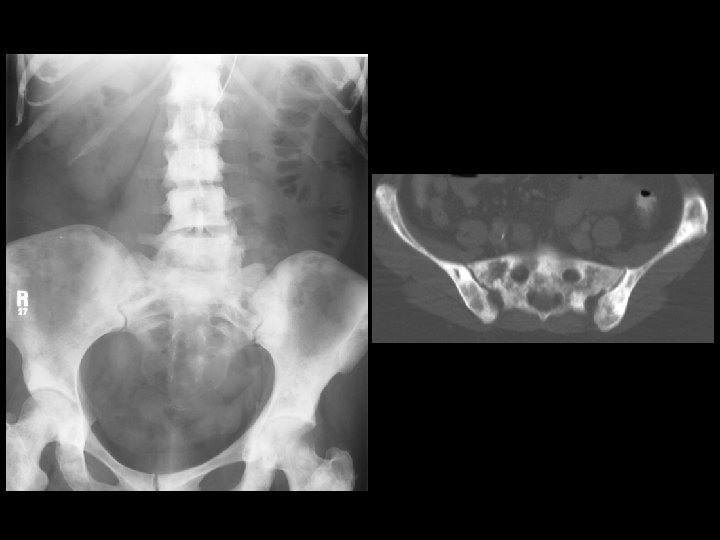

Paget’s Disease w/ sarcomatous degeneration • Findings: – Cortical thickening with mixed lytic and sclerotic trabecular pattern and bony enlargement – Large lytic lesion of the right ilium and sacral ala • ddx: – Diffuse sclerotic and lytic mets